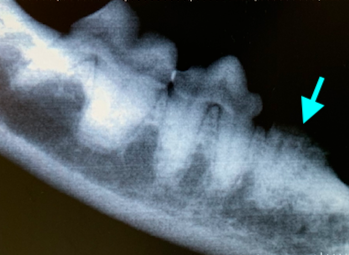

Резорбция зубов клинически часто проявляется отсутствием эмали и дентина зуба вблизи цементно-эмалевой границы, иногда она заполнена гиперплазированной десной и отмечается высокая кровоточивость при пальпации или зондировании этой области (фото 1).

Резорбтивные поражения могут локализоваться глубоко в альвеолах (поражается корень зуба), где происходит невоспалительная заместительная резорбция (корни зуба разрушаются и замещаются костью; фото 2).

При поражении коронки зуба имеется риск инфицирования зуба бактериями полости рта, что может привести к болезненному воспалению окружающих тканей (отек, боль, свищевые ходы, абсцедирование, остеомиелит; фото 3). Этиология этого заболевания у домашних кошек до сих пор не установлена. Существует несколько различных теорий, однако причинный фактор еще не определен.